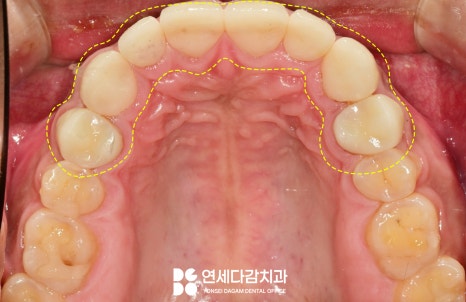

크라운은 치관 전체를

감싸 보호하는 보철로,

이것이 안정적으로

장착되기 위해서는

일정 두께가 확보되어야 됩니다.

따라서 전체적인 치관을 다듬고

정확성을 위해 경계선을 만들어

적합성을 확보합니다.

마진(margin)이 명확하지 않으면

보철물이 잇몸 깊숙이

삽입되거나 부정확하게 위치하여,

치은염이나 치주염 같은

치주 질환이 생길 수 있습니다.

또한 치은선과의 조화를

이룰 수 있도록 다듬어야

장착 시 자연스러운 모습을 볼 수 있습니다.